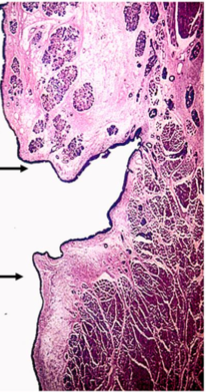

this is the larynx in the region of the ____

vestibular fold

2/ serous and mucuous glands

how do you know this is a vestibular fold of larynx?

respiratory epithelium with goblet cells and basal bodies